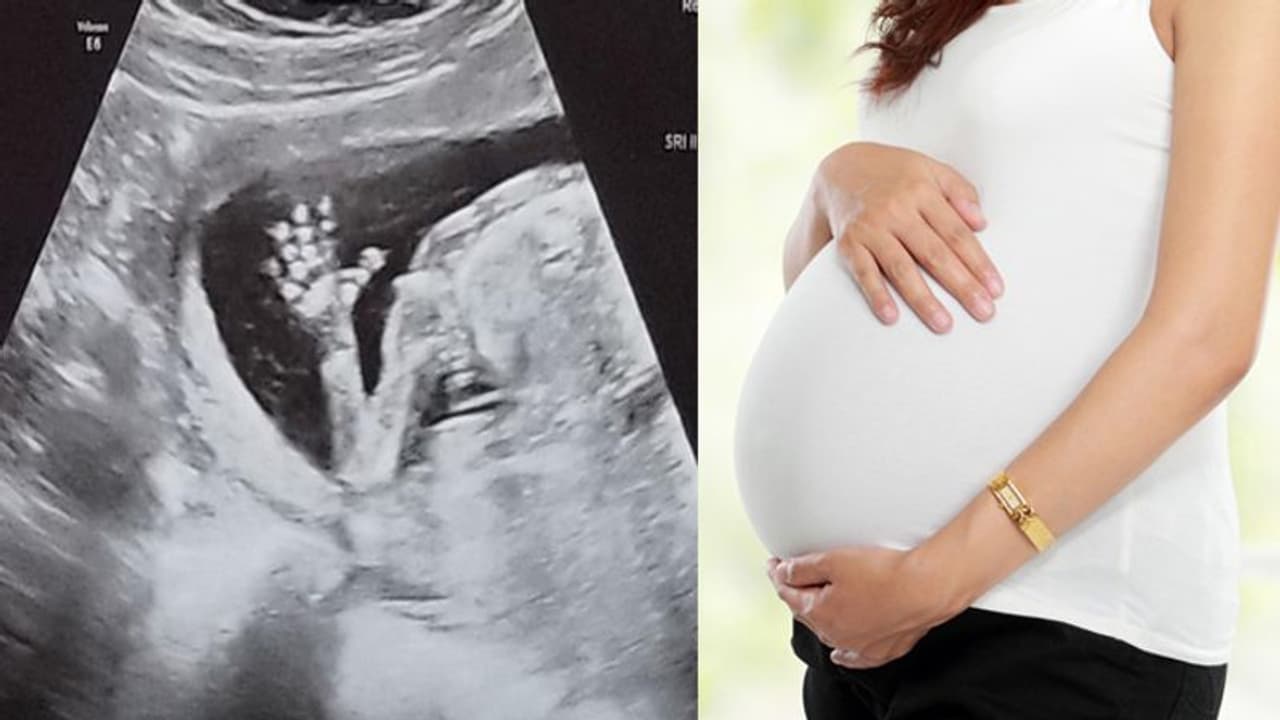

മിഷിഗണ്: ഗര്ഭിണിയായി പത്താം ആഴ്ചയിലെ അള്ട്രാസൗണ്ട് സ്കാനിംഗിലെ കണ്ടെത്തല് കണ്ട് ഞെട്ടി ആശുപത്രി ജീവനക്കാര്. മിഷിഗണ് സ്വദേശിയായ സ്കൂള് അധ്യാപികയുടെ സ്കാനിംഗിലെ വിവരങ്ങളാണ് അമ്പരപ്പിക്കുന്നത്. വളരെ അപൂര്വ്വമായി മാത്രം കാണുന്ന ശാരീരികാവസ്ഥയാണ് ഇരുത്തിയേഴുകാരിയായ ബെഥനിക്കുള്ളത്. ഒരാള്ക്ക് തന്നെ രണ്ട് യോനികളും രണ്ട് ഗര്ഭപാത്രവും അപൂര്വ്വ അവസ്ഥയാണ് യുവതിക്കുള്ളത്.

ഗര്ഭിണിയായപ്പോള് ബെഥനി അതീവ ശ്രദ്ധ പുലര്ത്തിയിരുന്നു. ഡോക്ടര് വിവരം പറഞ്ഞപ്പോള് യുവതിയും അമ്പരന്നു. രണ്ട് യോനിയും ഗര്ഭപാത്രവുമുള്ള വിവരം ഇത്രകാലത്തിനിടയില് ശ്രദ്ധയില്പ്പെടാതിരുന്നത് എങ്ങനെയാണെന്നാണ് യുവതി ചോദിക്കുന്നത്. ഈ അവസ്ഥ കണ്ടെത്തി ഏറെ വൈകാതെ തന്നെ ബെഥനിയുടെ ഗര്ഭം അലസിപ്പോവുകയും ചെയ്തു. ഇതോടെയാണ് ഇതിനേക്കുറിച്ച് വിശദമായി ബെഥനി പഠിക്കുന്നത്.

ചില സമയങ്ങളില് ഒരുമാസം തന്നെ രണ്ട് തവണ ആര്ത്തവും വന്നിരുന്നുവെങ്കിലും ഇത്തരമൊരു അസ്ഥ കാരണമായിരിക്കുമെന്ന് വിചാരിച്ചിരുന്നില്ലെന്ന് ബെഥനി പറയുന്നു. ആര്ത്തവ ദിനങ്ങളില് നിരവധി ബുദ്ധിമുട്ടുകള് നേരിട്ടിരുന്നുവെങ്കിലും അതെല്ലാം സാധാരണമായിരിക്കുമെന്നായിരുന്നു ബെഥനി കരുതിയിരുന്നത്. ബെഥനിയുടേതിന് സമാനമായ ശരീരഘടന മറ്റാര്ക്കും കണ്ടിട്ടില്ലെന്നാണ് ഡോക്ടര്മാര് പറയുന്നത്. ഇത്തരം അവസ്ഥയുള്ളവര്ക്ക് കുട്ടികള് ഉണ്ടാവുന്നത് ഏറെ ക്ലേശകരമെന്നാണ് ആരോഗ്യ വിദഗ്ധര് വിലയിരുത്തുന്നു.

അമ്മയാവാന് സാധ്യതയില്ലെന്ന് കൂടി അറിഞ്ഞതോടെ ബെഥനിയുടെ പ്രതീക്ഷകള് മങ്ങി. പക്ഷേ അപൂര്വ്വ അവസ്ഥയ്ക്ക് മുന്നില് കീഴടങ്ങാന് ബെഥനിയും ഭര്ത്താവും തയ്യാറായിരുന്നില്ല. വിവിധ ആശുപത്രികളിലെത്തി പരിശോധിച്ചു. ഡോക്ടര്മാരുടെ വിലയിരുത്തിലുകള് എല്ലാം തന്നെ സമാന രീതിയില് ആയിരുന്നു.

എന്നാല് രോഗ്യ വിദഗ്ധരെ വീണ്ടും അമ്പരപ്പിച്ചുകൊണ്ട് അപൂര്വ്വ അവസ്ഥ കണ്ടെത്തിയതിന് ഒരു വര്ഷം പിന്നിട്ടതോടെ ബെഥനി ഗര്ഭിണിയായി. ഒരു പെണ്കുട്ടിക്ക് ജന്മം നല്കുകയും ചെയ്തു. ഇത്തരം അവസ്ഥകളേക്കുറിച്ചുള്ള ബോധവല്ക്കരണ പ്രവര്ത്തനത്തില് സജീവമാണ് ബെഥനിയിപ്പോള്. മിഷിഗണിലെ അല് പാര്ക്കിലാണ് ബെഥനി താമസിക്കുന്നത്.